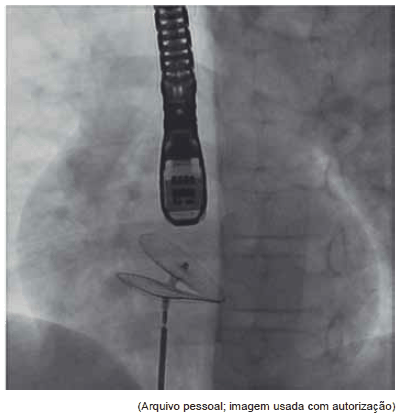

Observe as seguintes figuras.

Elas são compatíveis com qual diagnóstico?